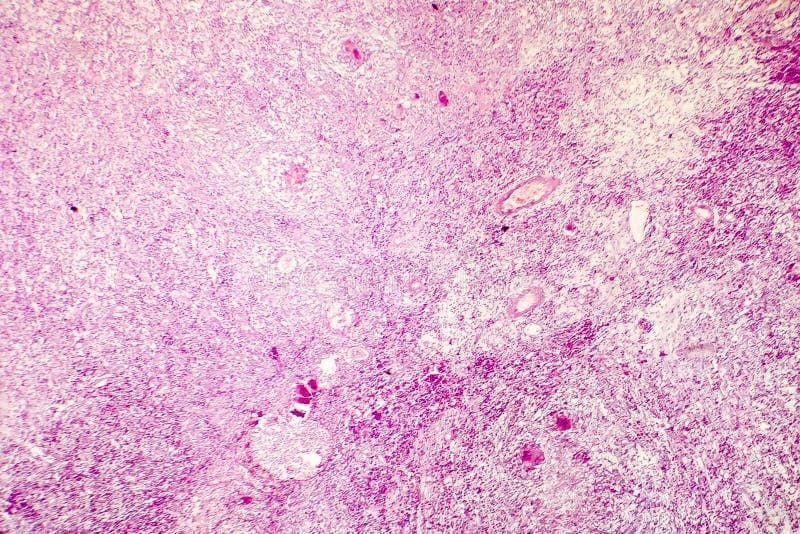

Coagulative necrosis is a pattern of irreversible cell death characterized by preservation of tissue architecture despite loss of cellular viability. It typically results from abrupt interruption of blood supply (ischemia) leading to acute infarction in solid organs such as the heart, kidneys, and spleen. Within minutes of ischemic injury, depletion of ATP impairs ion pumps, causing calcium influx and activation of degradative enzymes which denature structural proteins and enzymes. Because the degradative lysosomal enzymes themselves are inactivated by the denaturing environment, the basic outline of dead cells and tissue architecture remains intact for several days. Grossly, affected areas appear pale, firm, and wedge-shaped in the case of organ infarcts. Microscopically, coagulative necrosis shows eosinophilic cytoplasm, loss of nuclei, and preserved cell outlines. Over time, inflammatory cells infiltrate the damaged tissue, clearing debris and initiating fibroblast-mediated scar formation. This contrasts with liquefactive necrosis, where enzymatic digestion leads to tissue liquefaction, and with other necrosis types that display different morphological features. Recognizing coagulative necrosis provides important diagnostic clues to the timing and nature of ischemic injuries in pathological examinations and guides clinical management of infarctions.

Coagulative necrosis arises when tissue architecture remains intact despite irreversible cell death driven by protein denaturation. It most commonly follows abrupt interruption of blood flow—thrombosis, embolism, advanced atherosclerosis, vasospasm, sepsis-related arterial occlusion, or external compression—leading to ischemia and infarction in solid organs such as the heart, kidney, and spleen. Exogenous toxins, severe thermal injuries, chemical burns, and direct trauma can likewise produce coagulative changes by denaturing intracellular enzymes and structural proteins faster than lysosomal hydrolases can digest them. Clinically, patients present with organ‐specific symptoms and signs of inflammation: crushing chest pain and shortness of breath in myocardial infarction; flank or abdominal pain in renal and splenic infarcts; focal neurologic deficits in cerebral infarcts; or localized swelling, tenderness, and, in cutaneous injuries, blistering. Systemic manifestations often include low-grade fever and leukocytosis. Laboratory studies reveal elevated markers—troponin, creatine kinase, lactate dehydrogenase—when cardiac muscle is involved. Grossly, affected tissues appear pale, firm, and wedge-shaped, whereas microscopically they display homogeneous, eosinophilic cytoplasm, preserved cell outlines, and nuclear changes (pyknosis, karyorrhexis, karyolysis). Recognizing these causal factors and clinical features is essential for early diagnosis and intervention, since prompt restoration of perfusion or removal of the offending insult can limit tissue loss and improve patient outcomes.